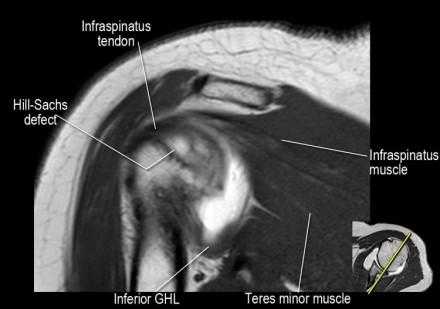

- обратите внимание на верхние отделы суставной губы и прикрепление верхней плече-лопаточной связки. На данном уровне ищется SLAP-повреждение (Superior Labrum Anterior to Posterior) и варианты строения в виде отверстия под сутавной губой (sublabral foramen - подгубное отверстие). На этом же уровне по задне-боковой поверхности головки плечевой кости визуализируются повреждение Хилл-Сакса.

- вогнутость заднебокового края головки плечевой кости не следует путать с повреждением Хилл-Сакса, поскольку это нормальная форма для данного уровня. Повреждение Хилл-Сакса визуализируется только на уровне клювовидного отростка. В предних отделах мы сейчас на урвоне 3-6 часов. Здесь визуализируются повреждение Банкарта и его варианты.

- обратите внимание на небольшое повреждение Хилл-Сакса